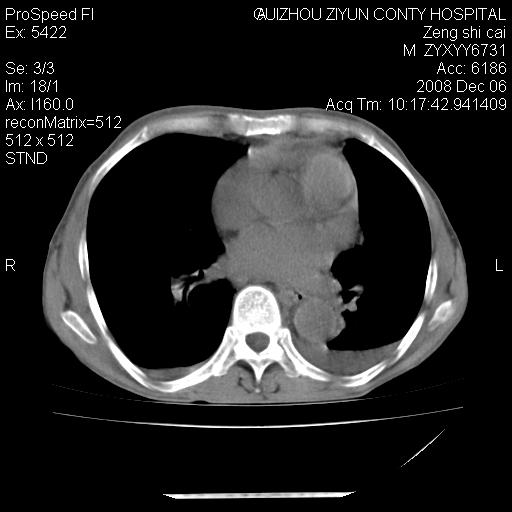

标题: CT16961:M、71岁,咳嗽半年,无血痰;胸片示右肺占位。 [打印本页]

标题: CT16961:M、71岁,咳嗽半年,无血痰;胸片示右肺占位。

1)考虑右肺上叶纵隔型肺癌伴纵隔淋巴结转移。2)心包积液,双侧胸腔积液。

右肺癌并纵隔淋巴转移,腹膜后转移可能性大,两侧胸腔积液

右肺上叶纵隔型肺癌伴纵隔淋巴结转移。心包积液,双侧胸腔积液。

右肺纵隔型肺癌伴纵隔淋巴结转移!双侧胸水\\心包积液